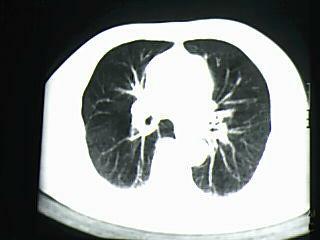

标题: CT19768:男 61岁 胸痛 咯血 一周。无发烧、无结核病史。 [打印本页]

标题: CT19768:男 61岁 胸痛 咯血 一周。无发烧、无结核病史。

右下肺中心型肺癌

右下肺支气管扩张

纵隔窗图像不佳,怀疑右下叶支气管有狭窄,来几张清楚的,暂考虑----感染性病变----抗炎后复查

考虑 右下肺感染性病变,建议抗炎后复查。

考虑右肺下叶感染性病变;建议抗炎治疗后复查。